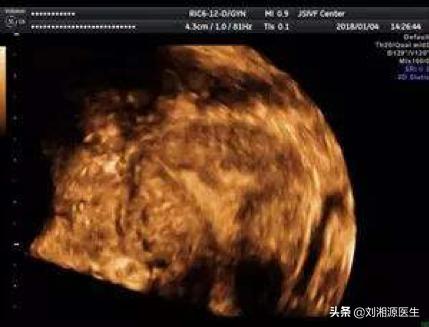

26.经阴道超声检查可发现宫腔粘连吗?

答:(1)目前应用的三维彩超,是诊断宫腔粘连的有效方法之一,因无创、方便、经济,临床广泛应用,能明确粘连部位及程度和宫腔内膜厚度。

(2)部分宫腔粘连时,三维彩超表现为子宫内膜厚薄不均、宫腔粘连处宫腔线消失和内膜薄,而粘连处以外内膜回声正常;

(3)宫腔广泛粘连时,三维彩超显示为宫腔内膜薄,呈细线状,内膜线中断,无周期性改变,或为不规则强回声。

(4)三维彩超不一定均能发现所有病变,敏感性52%,特异性仅11%。